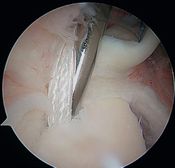

They reported that simple debridement allowed 85% of athletes to resume their sport at the same level (Figure and Video).

Simple labral debridement

Debridement of the labrum (Video) and superficial rotator cuff tears renders varying results depending on the author, ranging from 16% for Riand et al. to 85% for Andrews et al.. Labral tears can be left repaired (Figure), rotator cuff tears should not be repaired.[45][46]